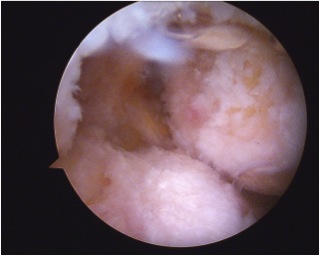

Right knee arthroscopy displaying empty medial femoral condyle. PCL jig has been placed and beath pin drilled outside in

PCL graft has been passed in right knee. ACL and PCL grafts passed